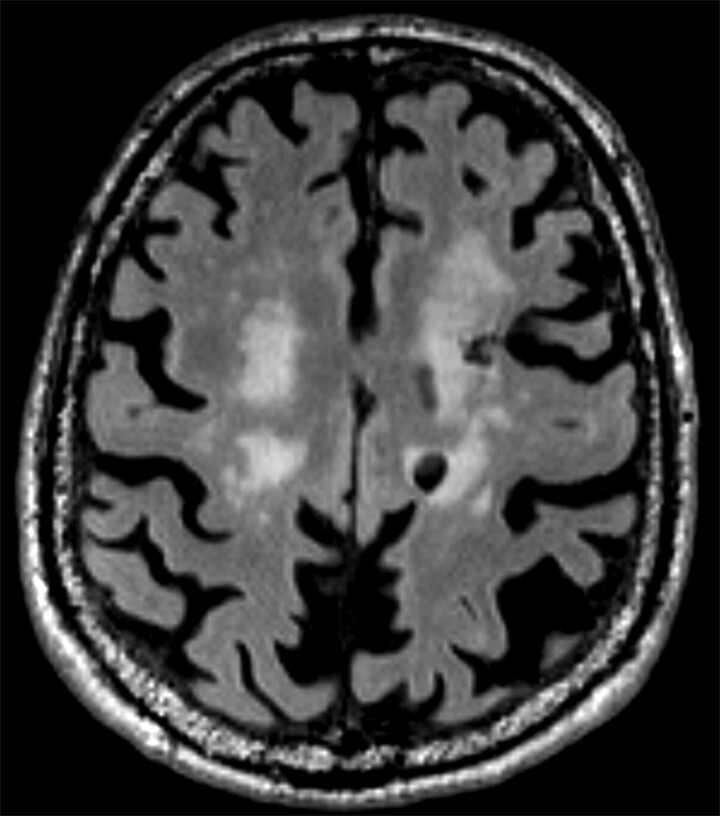

Abb. 69.3 Parkinson-Syndrome: Differenzialdiagnose subkortikale vaskuläre Enzephalopathie.

87-jähriger Mann mit Parkinson-Syndrom . ARWMC-Skala: White Matter 3 (diffus konfluierend) / Basalganglien 2 (mehr als eine fokale Läsion).

a T2w FLAIR-MRT-Sequenz. Fortgeschrittene subkortikale vaskuläre Enzephalopathie mit konfluierenden Marklagerläsionen im Centrum semiovale beidseits.

b Axiale Reformatierung einer 3-D-FLAIR-MRT-Sequenz. Zusätzliche Lakune im Putamen rechts sowie Narbe nach intrazerebraler Blutung im lateralen Putamen rechts. Der Stern kennzeichnet den strichförmigen Blutungsdefekt im Putamen.